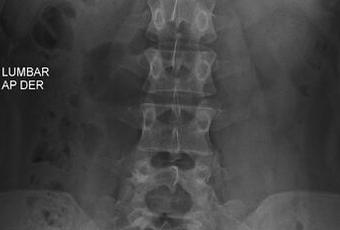

HALLAZGOS:

-Tejidos blandos, con densidad y morfología respetada, sin evidencia de lesiones.

-Columna vertebral, con convexidad hacia izquierda menor a 10°. Sin listesis. Lordosis lumbar, con adecuada angulación.

-Cuerpos vertebrales con altura preservada, sin evidencia de lesiones líticas, blásticas o perdida de la contigüidad. S1, con aspecto cuadrado y existiendo espacio intervertebral de manera significativa entre S1 y S2.

-Plataformas vertebrales, con adecuada densidad

-Pedículos, laminas posteriores sin evidencias de lesiones líticas, blásticas o perdidas de la contigüidad.

-Apófisis espinosas, transversas y facetas sin evidencias de lesiones líticas, blásticas o perdidas de la contigüidad.

-Espacio intervertebral con adecuada amplitud.

-Neuro forámenes con adecuada amplitud.

OPINIÓN RADIOLÓGICA:

EL PRESENTE ESTUDIO RADIOGRAFICO, CON ASIMETRÍA ESPINAL LEVOCONVEXA.

EXISTE LUMBARIZACION DE S1.

CORRELACIONAR CON DATOS E HISTORIA CLINICA DEL PACIENTE.